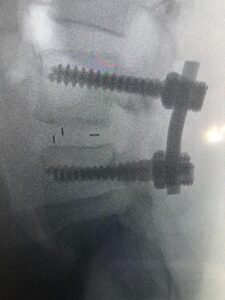

وأضاف د. أبو الراس بأنه تم إجراء العملية الدقيقة بعد موافقة المريضة عليها وعلى الخطة العلاجية ما بعدها، وتمثلت العملية في توسيع القناة العصبية واستئصال الغضروف ووضع دعامة بين الفقرات مع تصحيح الإنزلاق الفقاري وعمل دمج بين الفقرتين الرابعة والخامسة، وتكللت العملية بالنجاح -ولله الحمد- واستطاعت المريضة المشي في أول يوم لها بعد إجراء العملية.